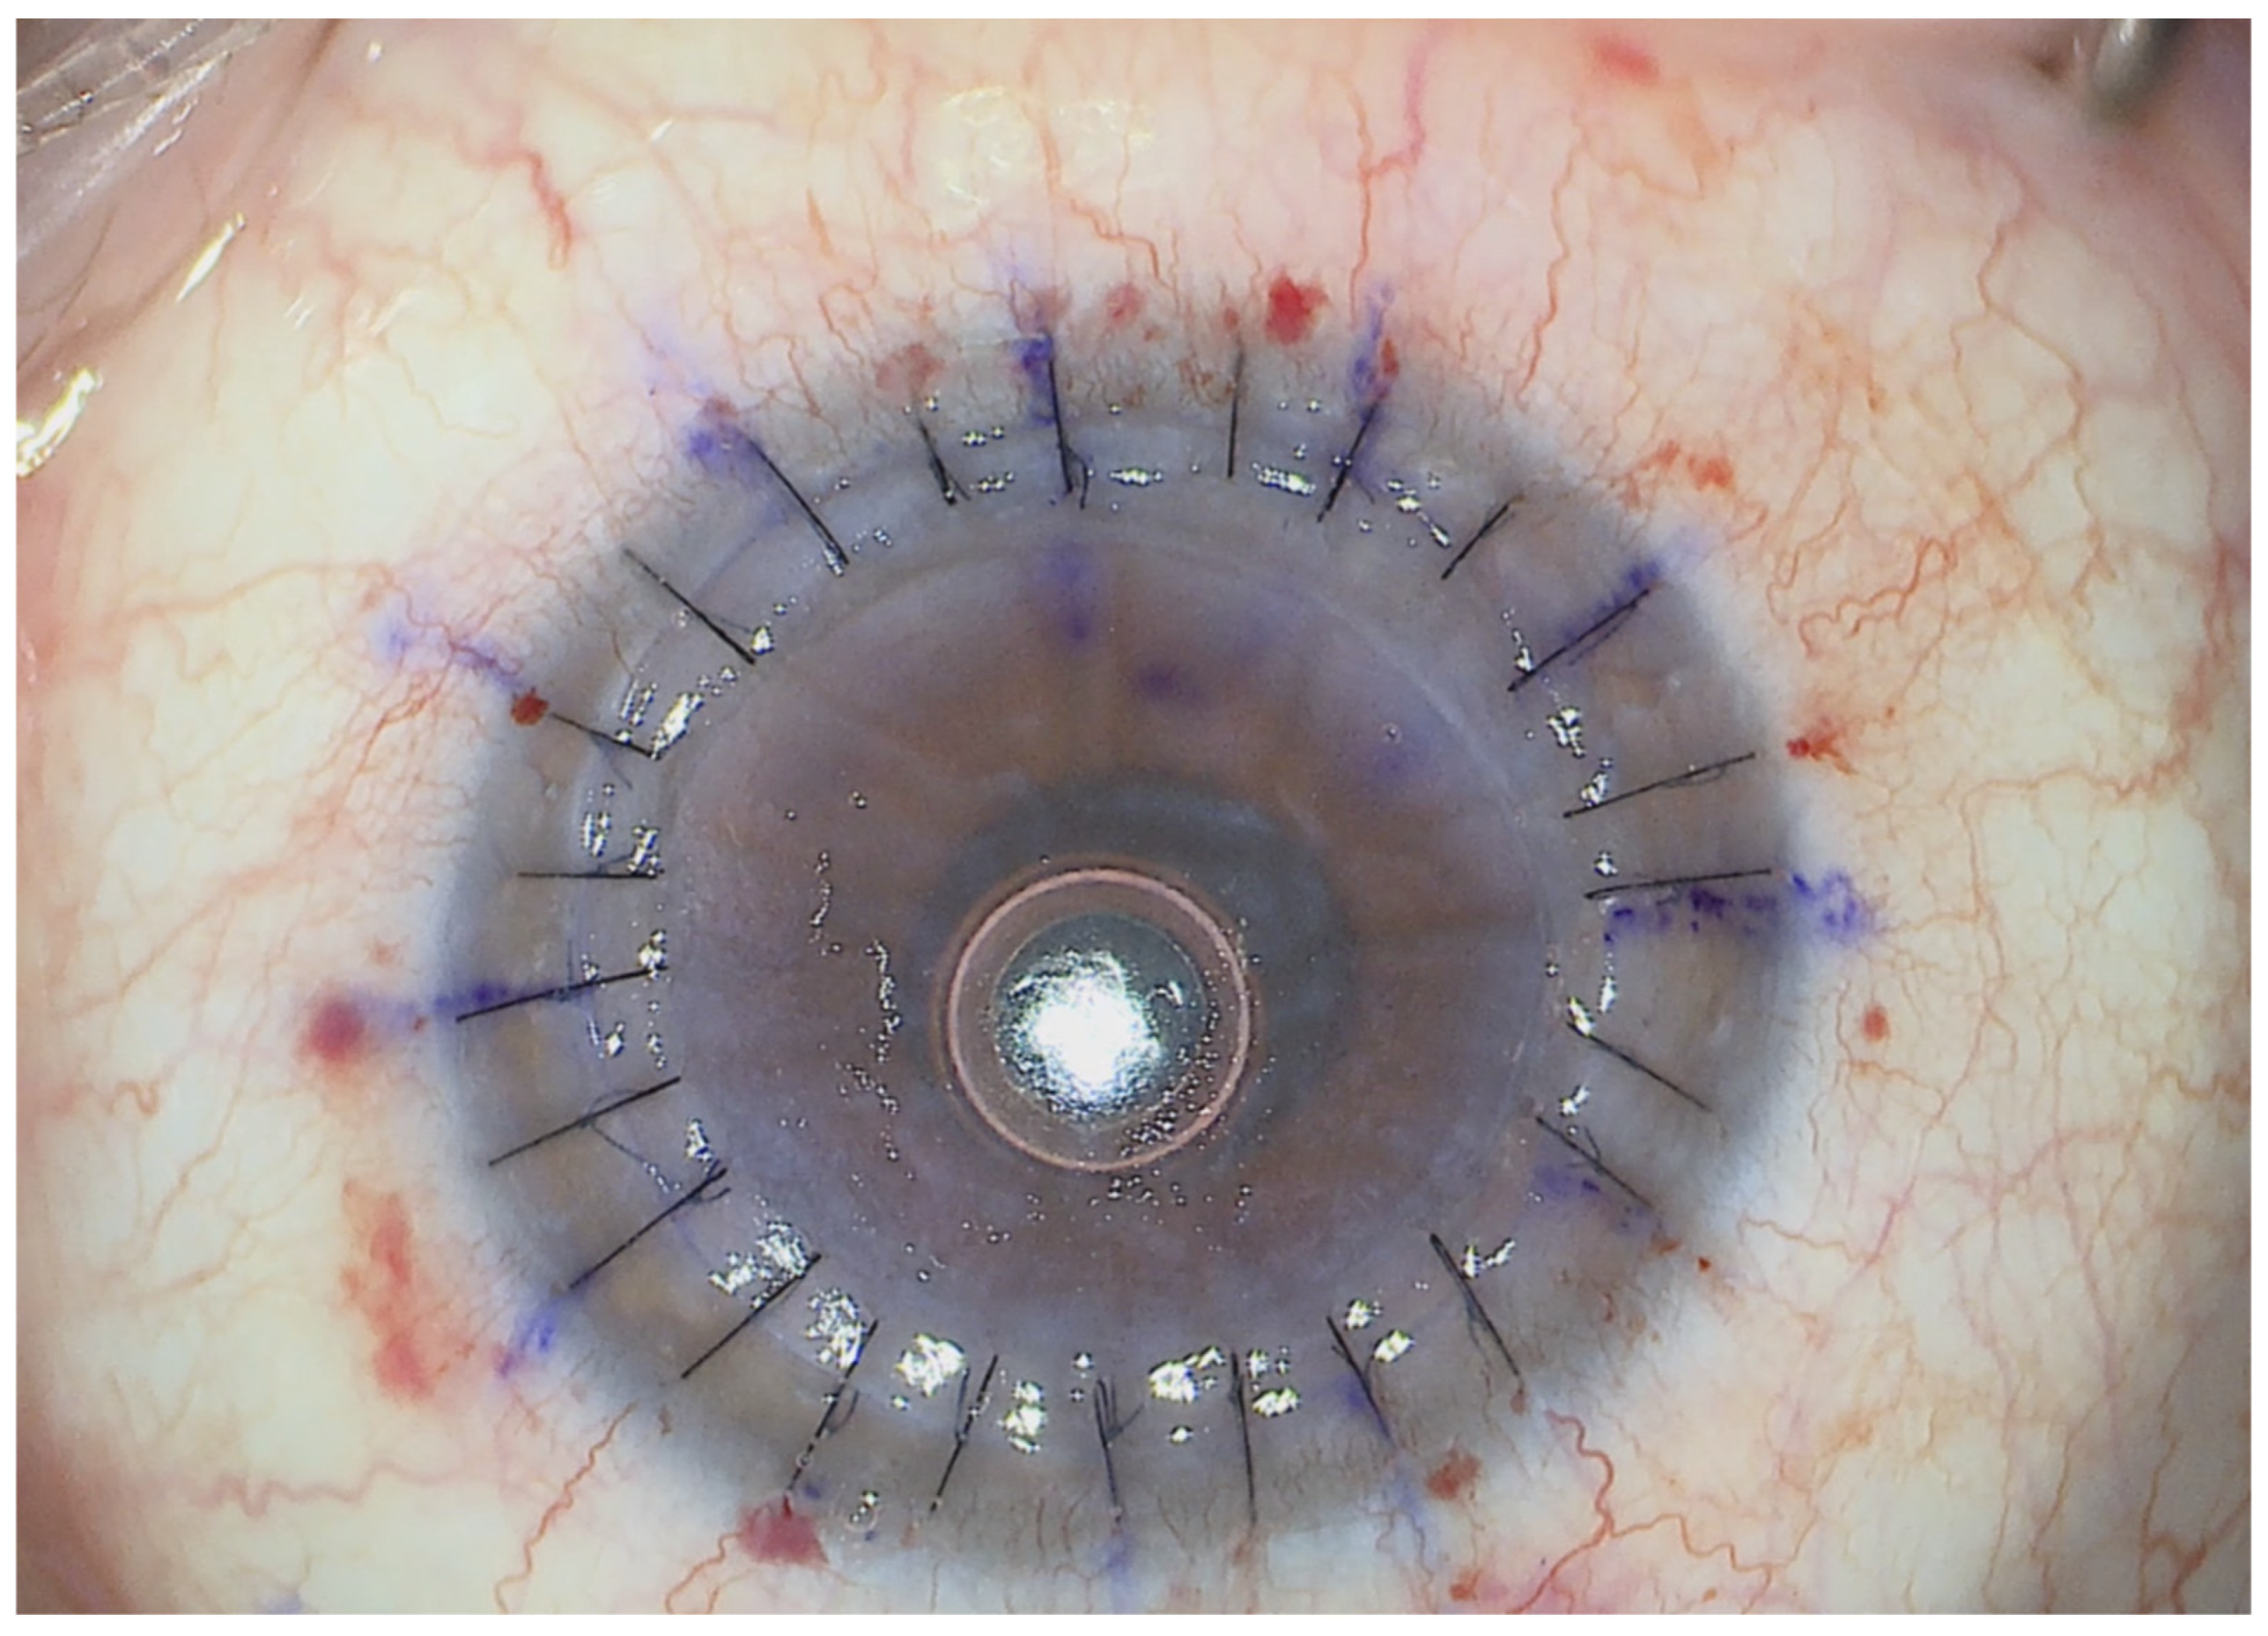

2. Materials and Methods

3. Technique

3.4. Graft Positioning and End of the Procedure